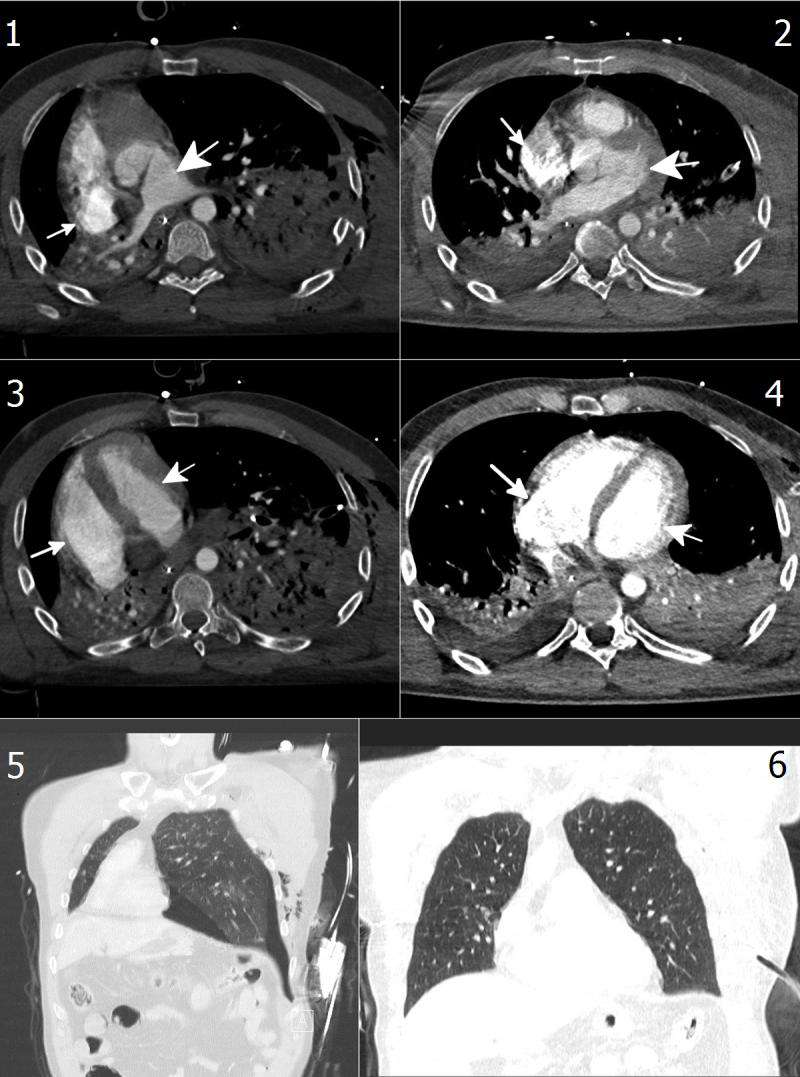

A chest radiograph and computed tomographic (CT) scan showed a 90-degree rightward rotation of the cardiac silhouette (Fig 1, Panel A, arrow) and great vessels (Fig 1, Panel C, arrows), with left tension pneumothorax and multiple rib fractures (Fig 2, Picture 1), bilateral pulmonary contusion (Fig 2, Pictures 1 and 3), and ruptured spleen.

A total-body CT scan showed rightward rotation of the pulmonary artery and aorta (Fig 1, Panel C), rotation of both atria (Fig 2, Picture 1), and rotation of both ventricles (Fig 2, Picture 3). The mediastinal shift that was caused by the tension pneumothorax (Fig 2, Picture 5) caused mild circulatory instability (blood pressure, 80/40 mm Hg; heart rate, 115 beats per minute; and oxygen saturation as measured by pulse oximetry, 92% while breathing 6 liters of supplemental oxygen) without neurologic impairment.

A total of 24 hours after pleural drainage, the patient’s heart moved leftward, back into its original position (Fig 1, Panel B, arrow), with complete anatomical and physiological recovery of the great vessels (Fig 1, Panel D, arrows) and other areas (Fig 2, Pictures 2, 4, and 6).